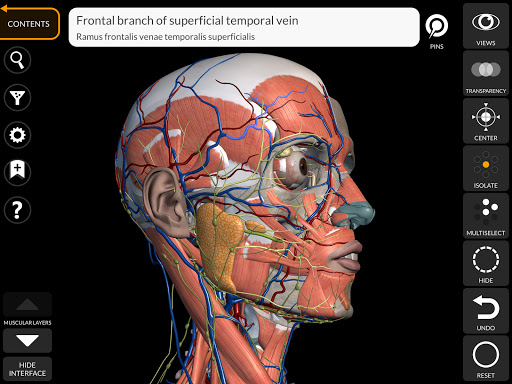

يتيح لك "Anatomy 3D Atlas" دراسة التشريح البشري بطريقة سهلة وتفاعلية.

من خلال واجهة بسيطة وبديهية، من الممكن ملاحظة كل بنية تشريحية من أي زاوية.

تتميز النماذج التشريحية ثلاثية الأبعاد بتفاصيل خاصة ودقة تصل إلى 4K.

يسهل التقسيم حسب المناطق والمناظر المحددة مسبقًا مراقبة ودراسة الأجزاء الفردية أو مجموعات الأنظمة والعلاقات بين الأعضاء المختلفة.

• الجهاز العصبي

• تصور العضلات من خلال مستويات الطبقات من الطبقات السطحية إلى الأعمق

• من خلال تحديد نموذج أو دبوس، يظهر المصطلح التشريحي ذي الصلة

• وصف العضلات: الأصل والإدخال والتعصيب والعمل

• يمكن عرض المصطلحات التشريحية بلغتين في وقت واحد